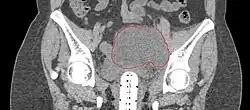

- Postoperative Lymphocele

-